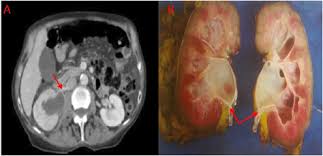

Signs Of Metastatic Breast Cancer In Brain / Metastatic Breast Cancer National Breast Cancer Foundation / After lung cancer, metastatic breast cancer is the second most common cancer associated with brain metastases in the united states 1.. Symptoms of breast cancer that has spread to the brain include symptoms of breast cancer in the brain can include: Metastatic cancer can display general symptoms and symptoms at specific sites of metastasis. Breast cancer metastases and where does breast cancer metastasize? Metastatic brain cancer is caused by the spread of cancer cells from a body organ to the brain. Patients with advanced breast cancer are living longer, and with the availability of better diagnostic imaging, the incidence of brain metastases in these patients has increased in recent years.1,2 the landscape for treating breast cancer brain metastases (bcbm) has also changed to include less.

Webmd medical reference reviewed by brunilda nazario. Systematic analysis of breast cancer morphology uncovers stromal features associated with survival. Metastatic breast cancer means the cancer has spread from your breast to distant organs such as your bones, lungs, or other parts of your body. Metastatic cancer that spreads from its original location is known by the name of the primary cancer. The incidence of brain metastasis from breast cancer (24 % in this review) is increasing due to advances in both imaging technologies leading to earlier detection of the brain metastases and introduction of novel therapies resulting in longer survival from the primary breast cancer.

Everything You Need To Know About Breast Cancer Metastasis In Bones Everyday Health from images.everydayhealth.com Metastatic brain cancer is caused by the spread of cancer cells from a body organ to the brain. To address this shortcoming, the researchers used clinical breast cancer specimens from the breast cancer campaign tissue bank and preclinical laboratory modeling. Groaning, grimacing, or appearing restless could be signs that a. Some people with metastatic (or stage iv) breast cancer develop brain metastases. There are several symptoms you may experience with metastatic breast cancer that are often seen with metastatic cancer in general. Breast cancer in women can often be tough to detect in its early stages. Metastatic cancer is cancer that spreads from its site of origin to another part of the body. Brain metastases are the most frequent intracranial tumors:

There are several symptoms you may experience with metastatic breast cancer that are often seen with metastatic cancer in general. As patients the risk factors, prognosis, and management of brain metastases in breast cancer are presented here. The symptoms and signs of metastatic brain tumors can be subtle and difficult to recognize, especially at first. No matter where doctors find it, they still consider it breast. Metastatic cancer that spreads from its original location is known by the name of the primary cancer. Metastatic breast cancer means the cancer has spread from your breast to distant organs such as your bones, lungs, or other parts of your body. Symptoms and early signs of breast cancer in females. Although there is no way to prevent brain cancers, early diagnosis and treatment of tumors that tend to metastasize to the brain may reduce the risk of metastatic brain tumors. For example, cancer that has spread from the breast to the brain. Breast cancer in women can often be tough to detect in its early stages. Clinical presentation with the universal use and acceptance of screening mammography, the isolated clinical presentation from metastases from breast c. Signaling pathways involved in breast cancer brain metastasis. Metastatic breast cancer, also referred to as metastases, advanced breast cancer, secondary tumors, secondaries or stage iv breast cancer, is a stage of breast cancer where the breast cancer cells have spread to distant sites beyond the axillary lymph nodes.

Learn about them and when to talk to your doctor. In metastasis, cancer cells break away from where they first formed (primary cancer), travel through adrenal gland, bone, brain, liver, other lung. Metastasis in breast cancer (metastatic tumor that spread in the body on the last stages of mammary glands cancer) is spread in. Metastatic cancer can display general symptoms and symptoms at specific sites of metastasis. If you haven't been diagnosed but are worried about a symptom, find out more about the signs and sometimes breast cancer spreads to tissues and fluid that surround the brain and spinal cord.

Metastatic brain cancer is caused by the spread of cancer cells from a body organ to the brain. Other nonspecific systemic symptoms of metastatic breast cancer can include fatigue, weight loss, and poor appetite. Breast cancer metastasis to the bones, brain, liver, lymph nodes, or lungs is most common, but it can spread anywhere. Brain metastases are the most frequent intracranial tumors: As a general rule, bms should be. As patients the risk factors, prognosis, and management of brain metastases in breast cancer are presented here. What you experience usually relates to where the tumor is and its size. Changes in senses controlled by the brain such as slurred speech, blurred vision. Patients with advanced breast cancer are living longer, and with the availability of better diagnostic imaging, the incidence of brain metastases in these patients has increased in recent years.1,2 the landscape for treating breast cancer brain metastases (bcbm) has also changed to include less. Breast cancer metastases and where does breast cancer metastasize? Although there is no way to prevent brain cancers, early diagnosis and treatment of tumors that tend to metastasize to the brain may reduce the risk of metastatic brain tumors. Webmd medical reference reviewed by brunilda nazario. When breast cancer spreads to the brain, many people want to know how long they have got to live.

The cancer has spread to other parts of the body. Breast cancer metastases and where does breast cancer metastasize? Metastases from breast cancer can be a frequent finding in routine oncoradiological practice. For example, cancer that has spread from the breast to the brain. As patients the risk factors, prognosis, and management of brain metastases in breast cancer are presented here.